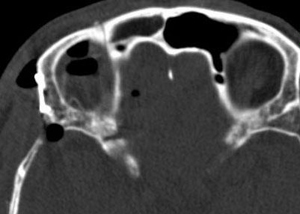

Ⅱ 60歳代男性

外眼筋四角錐内悪性リンパ腫

右視力・視野障害、眼球突出を主訴として来院した。摘出手術後視機能は改善し、眼球突出は消失した。骨条件術後CTでは、眼窩壁が整復され術前と同じ形状を維持していることがわかる。

術後 骨CT